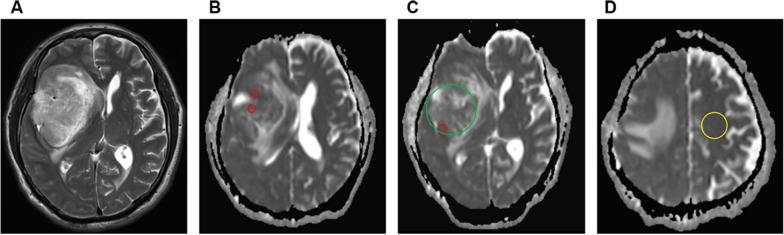

Ki-67 labeling index (LI) is an important indicator of tumor cell proliferation in glioma, which can only be obtained by postoperative biopsy at present. This study aimed to explore the correlation between Ki-67 LI and apparent diffusion coefficient (ADC) parameters and to predict the level of Ki-67 LI noninvasively before surgery by multiple MRI characteristics.

Preoperative MRI data of 166 patients with pathologically confirmed glioma in our hospital from 2016 to 2020 were retrospectively analyzed. The cut-off point of Ki-67 LI for glioma grading was defined. The differences in MRI characteristics were compared between the low and high Ki-67 LI groups. The receiver operating characteristic (ROC) curve was used to estimate the accuracy of each ADC parameter in predicting the Ki-67 level, and finally a multivariate logistic regression model was constructed based on the results of ROC analysis.

ADC, ADC, rADC, rADC and Ki-67 LI showed a negative correlation (r = - 0.478, r = - 0.369, r = - 0.488, r = - 0.388, all P < 0.001). The Ki-67 LI of low-grade gliomas (LGGs) was different from that of high-grade gliomas (HGGs), and the cut-off point of Ki-67 LI for distinguishing LGGs from HGGs was 9.5%, with an area under the ROC curve (AUROC) of 0.962 (95%CI 0.933-0.990). The ADC parameters in the high Ki-67 group were significantly lower than those in the low Ki-67 group (all P < 0.05). The peritumoral edema (PTE) of gliomas in the high Ki-67 LI group was higher than that in the low Ki-67 LI group (P < 0.05). The AUROC of Ki-67 LI level assessed by the multivariate logistic regression model was 0.800 (95%CI 0.721-0.879).

There was a negative correlation between ADC parameters and Ki-67 LI, and the multivariate logistic regression model combined with peritumoral edema and ADC parameters could improve the prediction ability of Ki-67 LI.